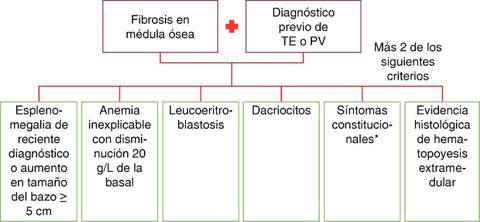

Existen formas de mielofibrosis secundaria, entre ellas las otras dos neoplasias mieloproliferativas mayores, metaplasia mieloide post-policitemia y metaplasia mieloide post-trombocitemia. El grupo internacional para la investigación y tratamiento de mielofibrosis (IWG-MRT por sus siglas en inglés) clarificó los criterios diagnósticos de estas dos entidades y fue adoptado por la OMS (Figura 6).2,9 Otras causas hematológicas incluyen leucemia de células peludas, linfoma y mieloma múltiple. En las formas de mielofibrosis no hematológicas se encuentra la invasión metastásica de la médula ósea, enfermedades autoinmunes (lupus eritematoso sistémico, esclerodermia, enfermedad del tejido conectivo, polimiositis), hiperparatiroidismo secundario, entre otras.9

Figura 5: Diagnóstico para mielofibrosis.